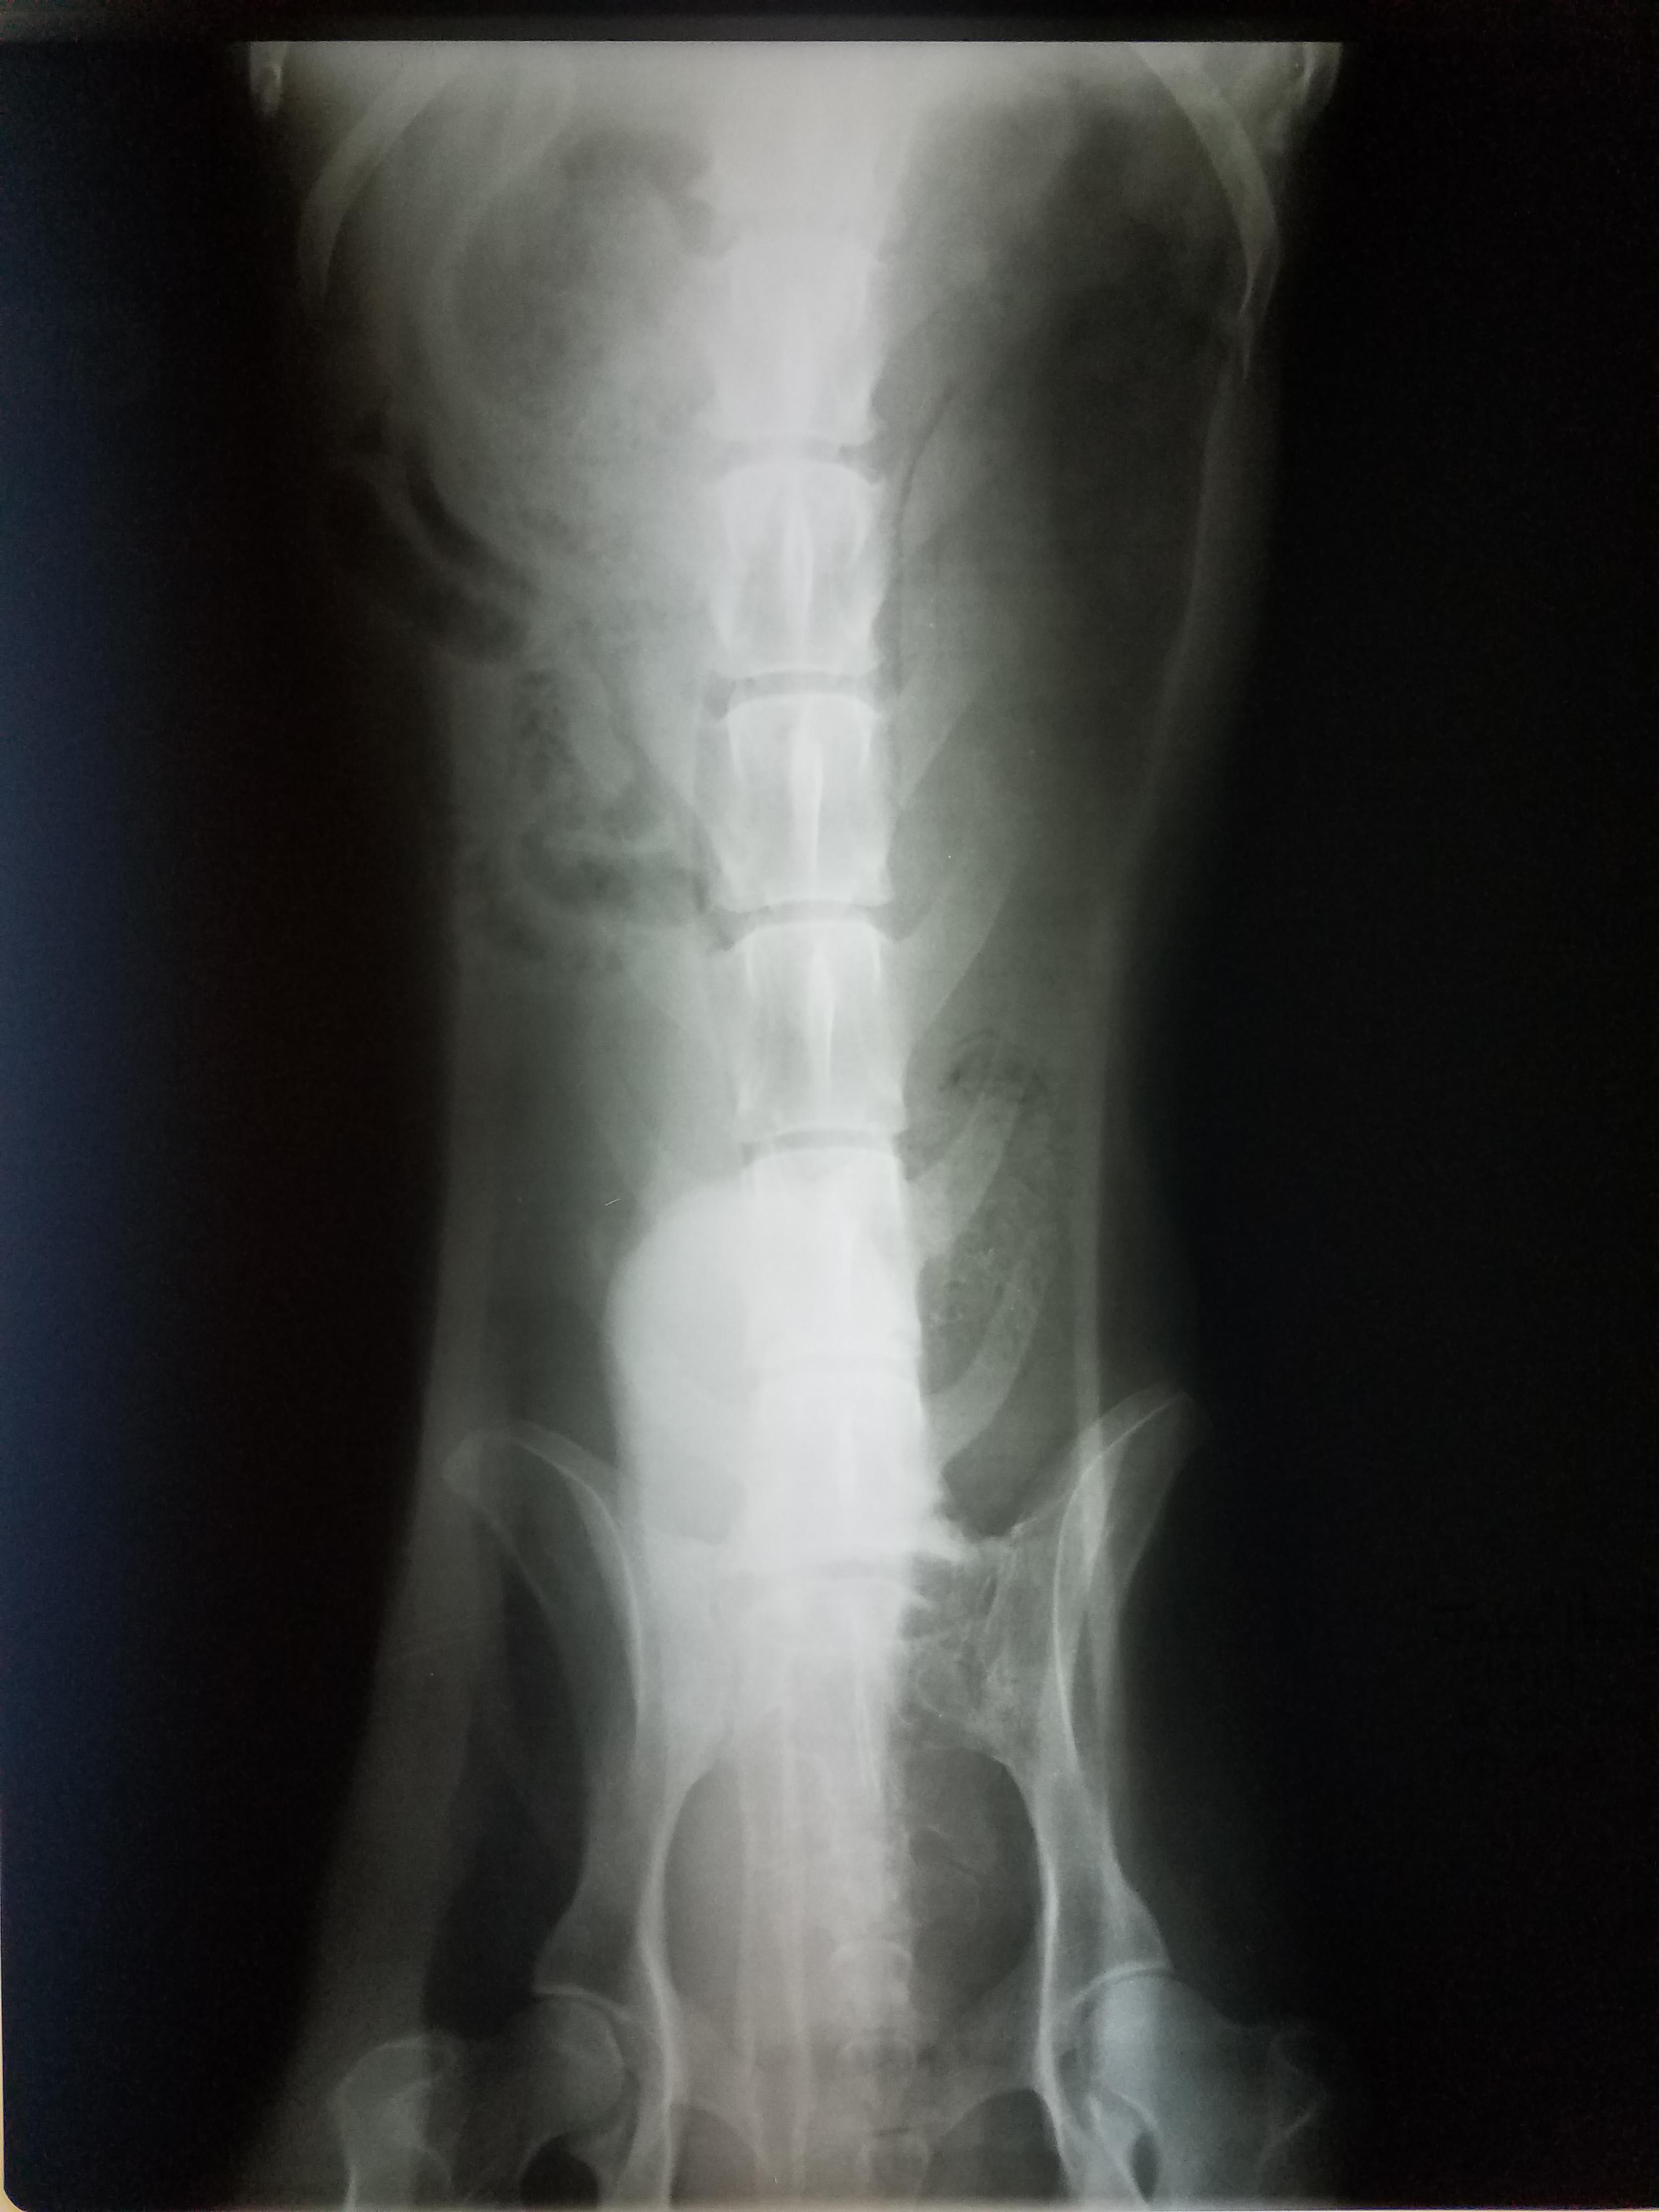

Senior dog has enlarged testicles, swollen legs, and high WBC. Is it cancer?

Pet's info: Dog | German Shepherd | Male | 10 years and 7 months old | 98 lbs

I keep getting conflicting answers. Vet said he has colorectal or prostate cancer. Two here say gas and feces build up. His testicles are like orange size and Dr said swell in back legs is called edema compromised circulation. Vets here don't have the patient and can go only by the attached x-rays. He also has impacted fistulas. Dr recommend euthenasia. Gas build up isn't the same as cancer Blood work shows wbc 43.35 see attached

It sounds like prostatitis and/or cancer. I'm not exactly sure what your question is. We don't have enough information to be able to guide you to a decision. I do not think it is simple gas/constipation. The fistulas and the size of the testicles is very concerning. I think you should consider taking him to an internal medicine specialist for a consult. ( https://www.gcvs.com/service/internal-medicine/ ) ( https://urbananimalveterinary.com/services/internal-medicine/ )